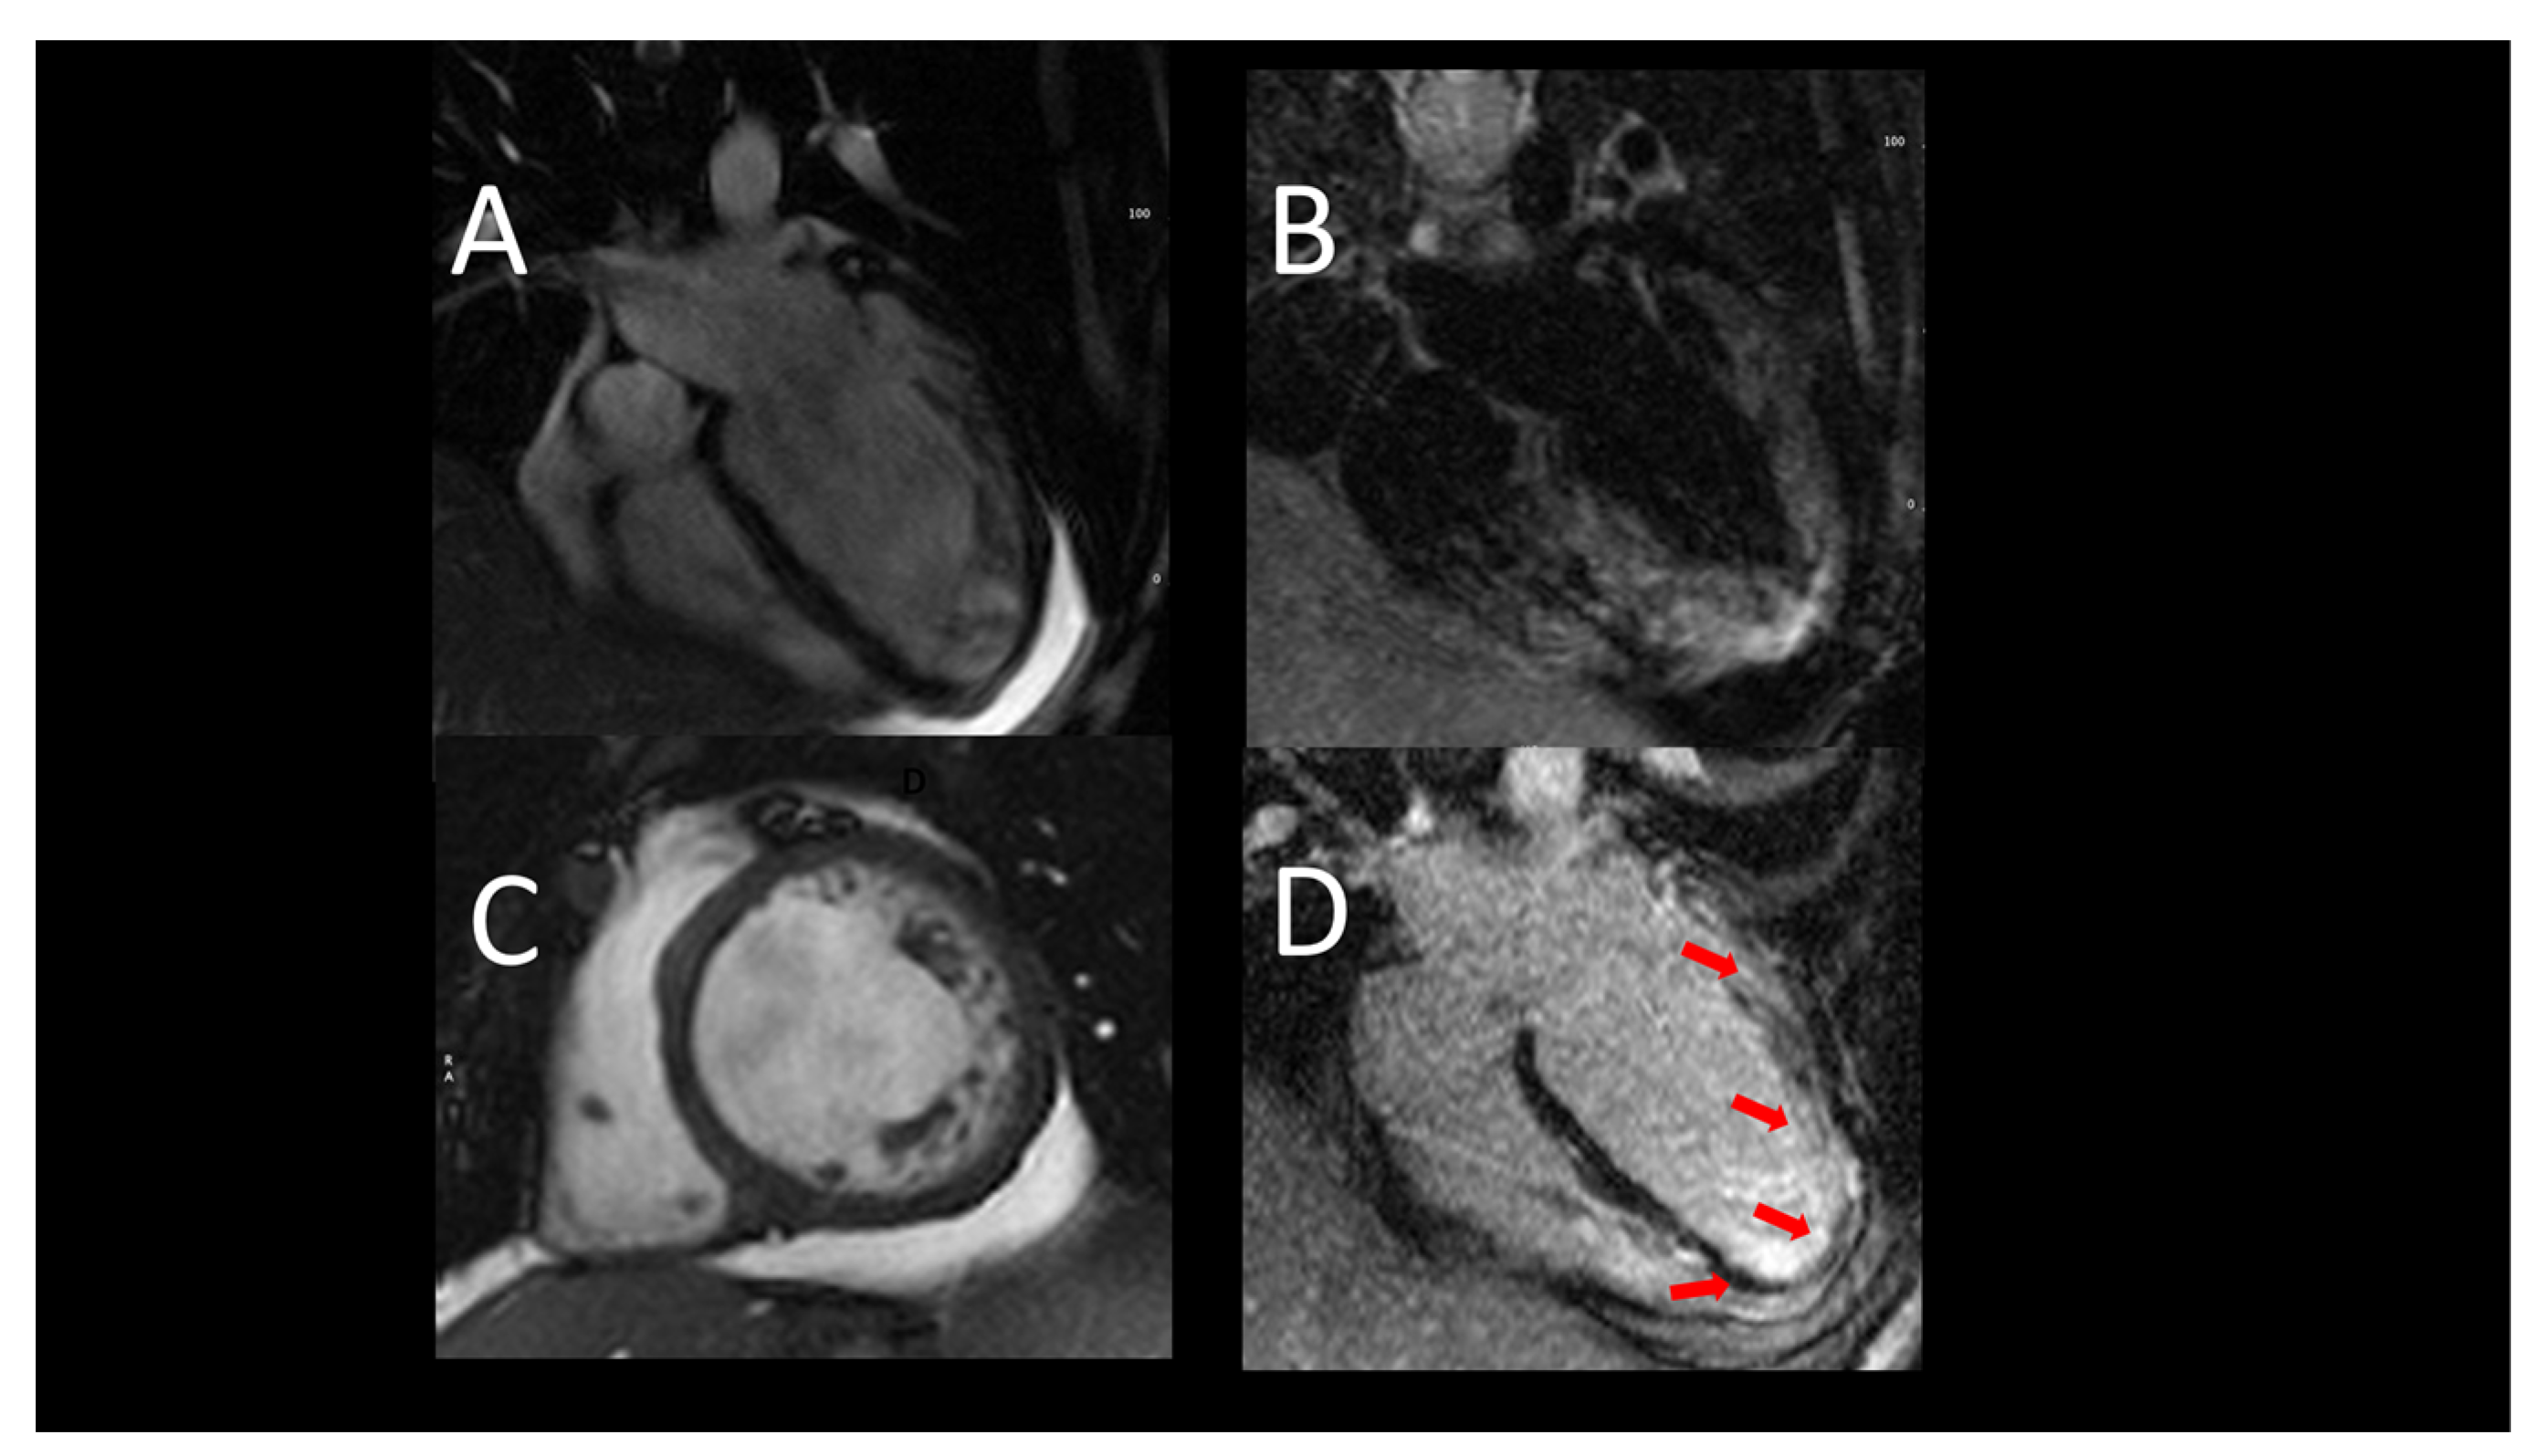

2.1.2. Role of Cardiac Magnetic Resonance Imaging in AHF

- Contaldi, C.; Dellegrottaglie, S.; Mauro, C.; Ferrara, F.; Romano, L.; Marra, A.M.; Ranieri, B.; Salzano, A.; Rega, S.; Scatteia, A.; et al. Role of Cardiac Magnetic Resonance Imaging in Heart Failure. Heart Fail. Clin. 2021, 17, 207–221. [Google Scholar] [CrossRef] [PubMed]

- Vöhringer, M.; Mahrholdt, H.; Yilmaz, A.; Sechtem, U. Significance of Late Gadolinium Enhancement in Cardiovascular Magnetic Resonance Imaging (CMR). Herz 2007, 32, 129–137. [Google Scholar] [CrossRef] [PubMed]

- Memon, S.; Ganga, H.V.; Kluger, J. Late Gadolinium Enhancement in Patients with Nonischemic Dilated Cardiomyopathy. Pacing Clin. Electrophysiol. 2016, 39, 731–747. [Google Scholar] [CrossRef]

- Aquaro, G.D.; De Gori, C.; Faggioni, L.; Parisella, M.L.; Cioni, D.; Lencioni, R.; Neri, E. Diagnostic and prognostic role of late gadolinium enhancement in cardiomyopathies. Eur. Heart J. Suppl. 2023, 25, C130–C136. [Google Scholar] [CrossRef]

- Nagueh, S.F.; Nabi, F.; Chang, S.M.; Al-Mallah, M.; Shah, D.J.; Bhimaraj, A. Imaging for implementation of heart failure guidelines. Eur. Heart J. Cardiovasc. Imaging 2023, 24, 1283–1292. [Google Scholar] [CrossRef] [PubMed]

- Karamitsos, T.D.; Piechnik, S.K.; Banypersad, S.M.; Fontana, M.; Ntusi, N.B.; Ferreira, V.M.; Whelan, C.J.; Myerson, S.G.; Robson, M.D.; Hawkins, P.N.; et al. Noncontrast T1 Mapping for the Diagnosis of Cardiac Amyloidosis. JACC Cardiovasc. Imaging 2013, 6, 488–497. [Google Scholar] [CrossRef]

- Markatis, E.; Afthinos, A.; Antonakis, E.; Papanikolaou, I.C. Cardiac sarcoidosis: Diagnosis and management. Rev. Cardiovasc. Med. 2020, 21, 321–338. [Google Scholar] [CrossRef] [PubMed]

- Child, N.M.; Das, R. Is cardiac magnetic resonance imaging assessment of myocardial viability useful for predicting which patients with impaired ventricles might benefit from revascularization? Interact. Cardiovasc. Thorac. Surg. 2012, 14, 395–398. [Google Scholar] [CrossRef] [PubMed]

- Katikireddy, C.K.; Samim, A. Myocardial viability assessment and utility in contemporary management of ischemic cardiomyopathy. Clin. Cardiol. 2022, 45, 152–161. [Google Scholar] [CrossRef] [PubMed]